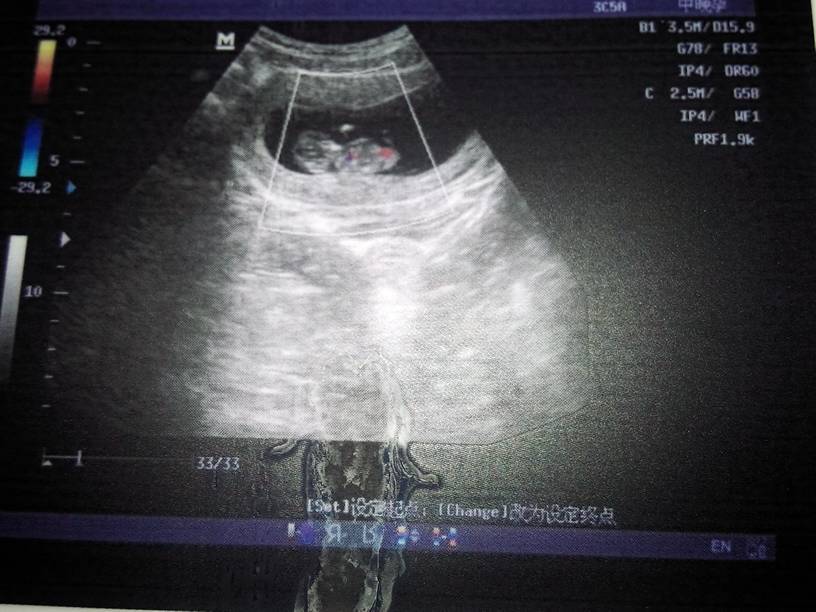

我11+1周,头臀径为41cm,其余正常,能看出男女吗 我11+1周,头臀径为41cm,其余正常,能看出男女吗 点击展开 神马都是浮云_McEd 2014-07-31 16:59 为您推荐: 其他回答 不客气 王红是我abc 2014-08-30 20:52 你好,这个是看不出孩子的性别的,才几周,看不出来的,要等再大一点才可以看出来的。 王红是我abc 2014-07-31 17:34 相关问题 怀孕10周,孕囊大小为52x44mm 头臀径为31mm,请问正常么?能看出男女不能? 现在12周加六天,宝宝能看出男女了吗 17周谁能准确的告诉我能不能看出男女?